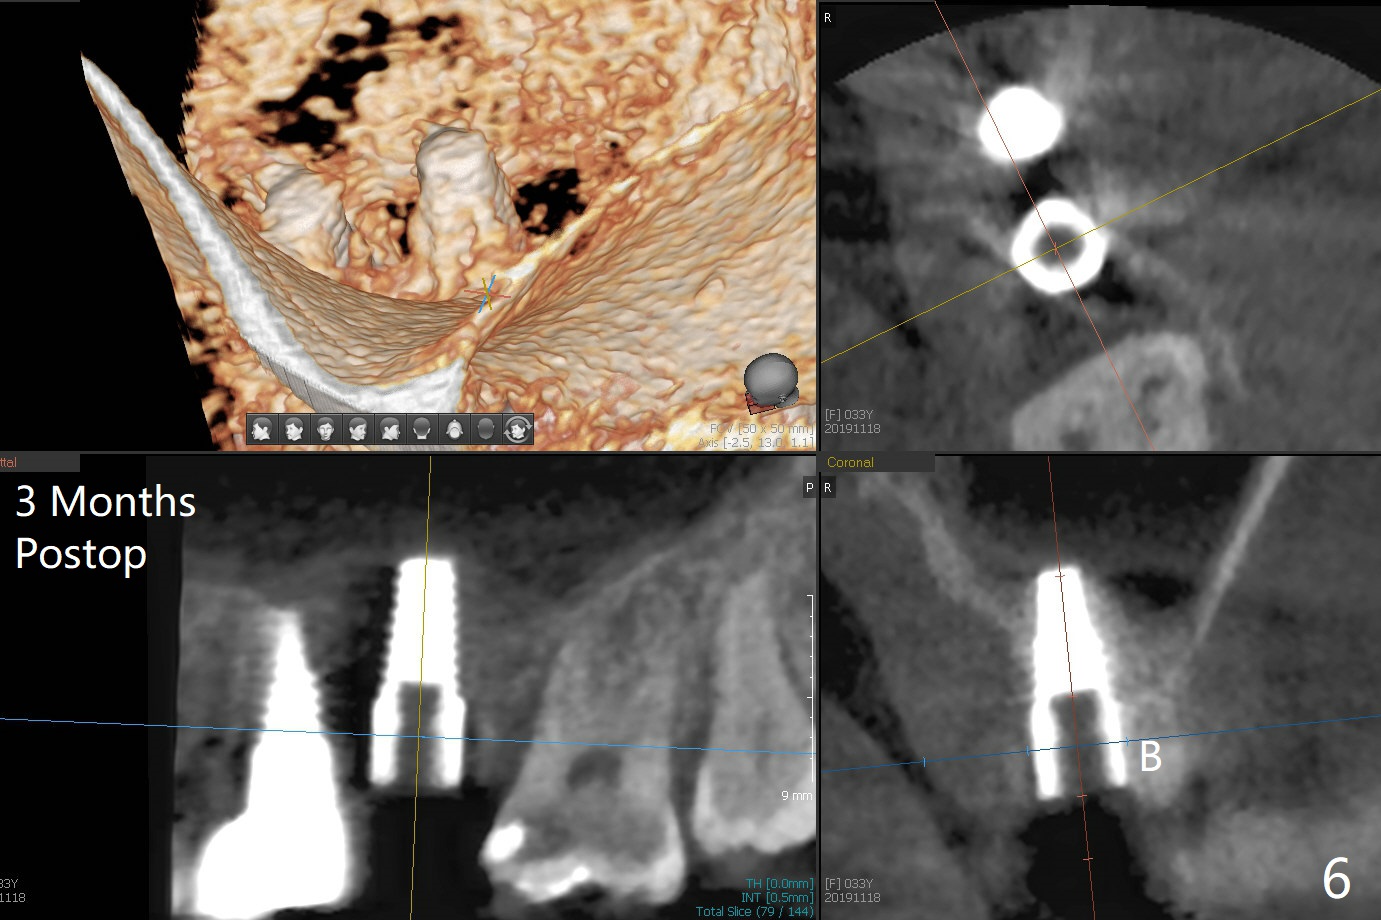

The ridge at #14 seems wide 6 months post implant removal and bone graft (before and after incision). In fact the palatal bone is low, which was the basis for periimplantitis. The new osteotomy is not initiated buccal enough. Immediate redo or guided surgery can avoid this complication. When a 4.5x14 mm tap is placed (Fig.1), the palatal threads are exposed. The buccal bone of the osteotomy has to be removed before placement of a 4.5x11 mm with 1 thread exposure palatal (Fig.2). Periimplantitis at #13 is found intraop (Fig.1 *). After removal of granulation tissue and use of Titanium brush, allograft is placed at #13 and 14 (Fig.2 ^) and is covered by PRF. Bone expansion is not conducted because of high bone density. If there is difficulty in restoration due to deep implant placement, it has to be backed up using torque wrench. The wound appears to heal by secondary intention 20 days postop (Fig.3). The implant is subgingival nearly 3 months postop (Fig.4 ^: gingival margin). It appears that the implant could be backed up (Fig.5,6). A 5 mm healing cuff is placed with Cetacaine and antibiotic ointment. The implant remains subgingival with the healing abutment 4 months postop. With Cetacaine and 2 gingival retraction cords, the implant margin is barely exposed. Large and deep gingivectomy is performed with Waterlase without too much pain. The gingival cuff is slightly erythematous and hemorrhagic on cementation (partially due to suboptimal oral hygiene, Fig.7). The margin is deep. Tatum implants are contraindicated when the gingiva is thick (Fig.8).